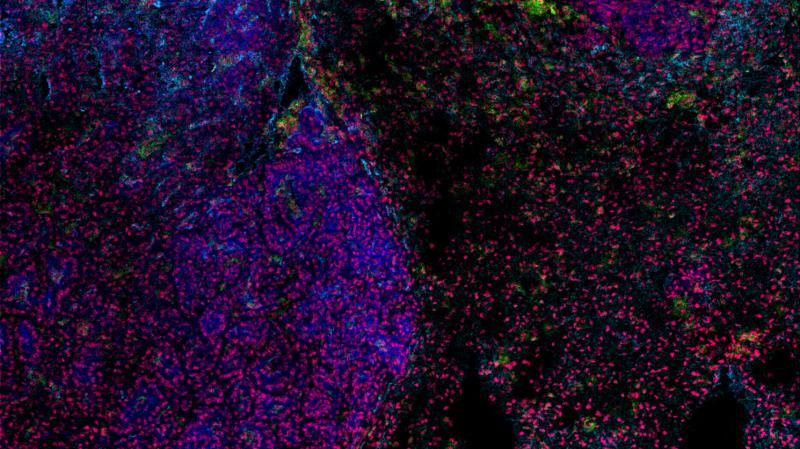

Κύτταρα του ανοσοποιητικού συστήματος που εμφανίζονται με πράσινο χρώμα συγκεντρώνονται στα όρια όγκου (Francis Crick Institute)